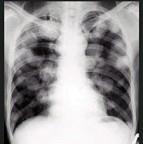

问题 男,45岁,HBV阳性10年,胸痛1个月伴咳嗽,咯血1天,胸片如图,选择最可能的诊断 ( )

选项 A.肺多发性脓肿 B.肺韦格肉芽肿 C.HBV病毒肺部转移 D.金葡菌感染 E.肺转移癌

答案 E